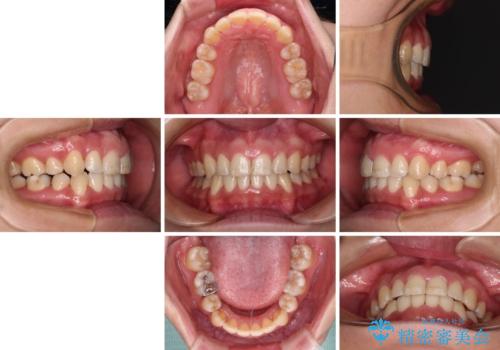

前歯のデコボコを短期間で解消 ワイヤー装置による抜歯矯正

- 上下前歯のデコボコを気にして来院された患者様です。

デコボコが強いため、非抜歯で矯正をすると出っ歯仕上がりとなるため、上下左右の第一小臼歯4本を抜歯することとしました。

当初予定は2年半程度と伝えていましたが、2年にも満たない期間で治療を終えることができました。